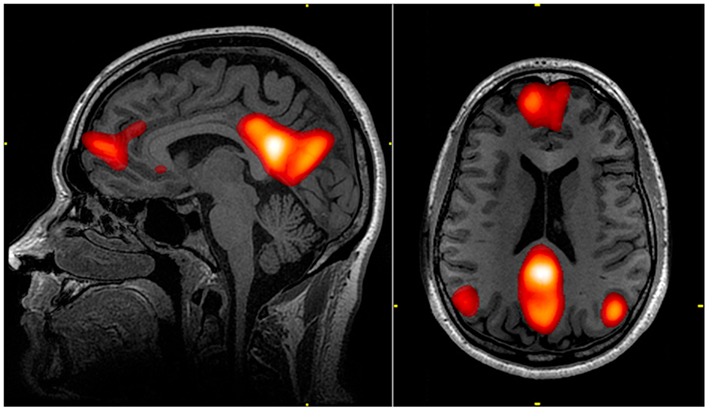

③ 반복적 상상과 이미지

미래를 구체적으로 떠올리는 과정은

DMN, 전전두엽, 해마를 동시에 활성화해

새로운 무의식 패턴을 학습하게 만든다.